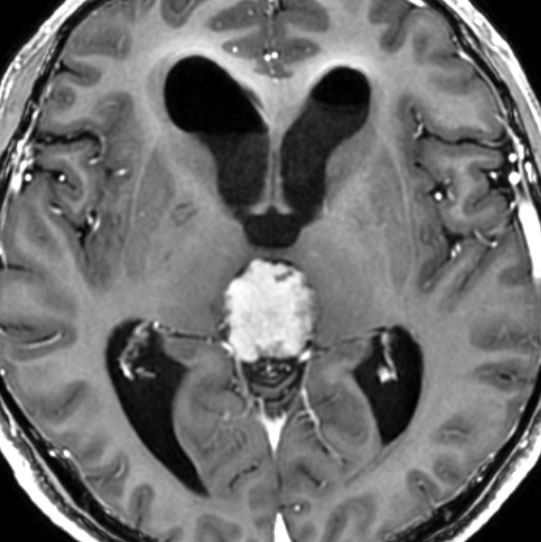

40代男性のPPTIDグレード3です。早朝の激しい頭痛で発症しました。morning headacheは松果体腫瘍の特徴でもあります。これに対して内視鏡による第3脳室開窓術と生検術がなされてから紹介されてきました。生検術前のHCG-beta 2.1mIUと陽性でしたからgerminomaを強く疑いましたが,生検病理診断はrosette構造があり中等度の核異型を有するPPTIDであり,MIB-1 8%でした。短期間の間に増大していました。グレード3 PPTIDと判断されます。

第3脳室開窓後のCTです。左のCTでは小さな石灰化がみられます。右の造影CTでは小さなのう胞部分をのぞいて均一な増強効果がみられます。

MRIガドリニウム増強像です。腫瘍境界がわりにはっきりしていて,中脳や視床に浸潤像がありませんから,松果体芽腫ではないことが解ります。でも,この画像だけからは,松果体細胞腫やジャーミノーマとの区別はつきません。